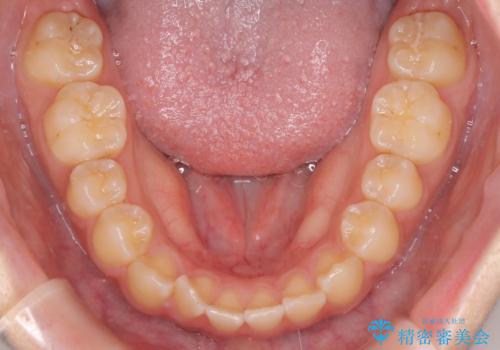

- 前歯の叢生を主訴に来院されました。非抜歯でインビザラインで治療をしました。

叢生はIPRをし、並べました。この患者様はオープンバイトだったため歯を並べる過程でかみ合わせも治しました。